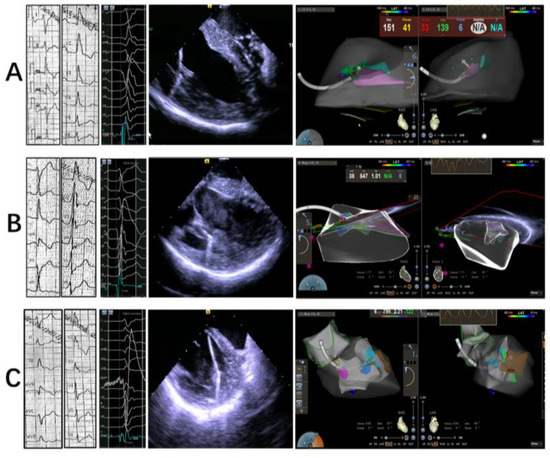

2.2. Electrophysiology Study, Mapping and Ablation

2.2.1. Intracardiac Echocardiography

2.2.2. Mapping and Ablation